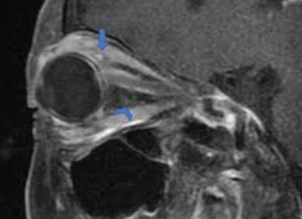

Visual acuity and visual field tests are a good screen to test for chiasmal involvement. Neuroimaging may also be needed (i.e. MRI (magnetic resonance imaging)). In some cases, endocrinologic evaluation should be considered when the cause is pituitary adenoma, which is the most common extrinsic cause of chiasmal syndrome. A pattern electroretinogram may be measured to predict the visual prognosis of patients with chiasmal compression.

The progression of the injury can cause compression of adjacent structures, including the optic nerves and cavernous sinus, resulting in further vision loss, oculomotor nerve deficits and hypopituitarism.